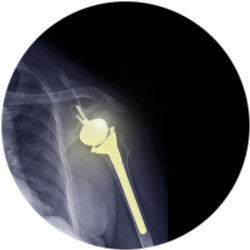

Эндопротезирование плечевого сустава

Операция проводится лицам мужского и женского пола после индивидуальной консультации и детальной подготовки. В зависимости от клинического диагноза и степени повреждения плечевого сустава врач подбирает подходящий метод эндопротезирования. Так, при тотальном протезировании заменяется плечевая головка, лопаточная впадина и костные структуры. Однополюсное эндопротезирование предполагает замену только одного компонента плечевого сустава: головки или впадины лопатки. При поверхностном протезировании меняют лишь хрящевую часть кости.